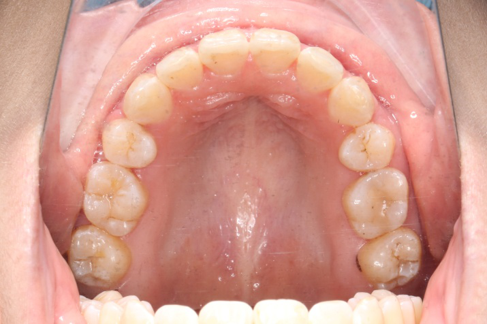

2018.11.14  术后磨牙尖牙I类关系,中线齐,覆合,覆盖正常

2019.08.06  术后  10个月复查

宏观评价:面部对称,面下三分一比例协调,上下唇凸度正常,上颌牙列内收转矩控制良好,下颌后缩改善,颏唇沟变得更加柔和,术后达到基本直面型。

迷你观评价:上下牙齿中线与面中线对齐,笑弧协调,微笑时牙龈暴露量正常,微笑时横向正常,左右唇基本对称。

微观评价:牙齿整齐,咬合关系良好,上下前牙转矩及突度控制良好,磨牙关系I类,尖窝咬合关系良好,OB,OJ正常。